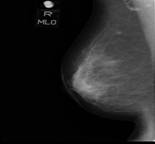

マンモグラフィでは、乳房を圧迫し、上下、左右の2方向から撮影を行います。乳房を圧迫することで、より診断しやすい写真になりますが、圧迫によって痛みの生じる方もおられます。 このため、「マンモグラフィは痛い」と聞いて検査をためらう方も多いと思われますが、痛みには個人差があり、また、緊張せずにリラックスして検査を受けていただいたくことで、痛みはかなり軽減するといわれています。乳房が張る生理前を避けて検査を受けていただくことも重要です。